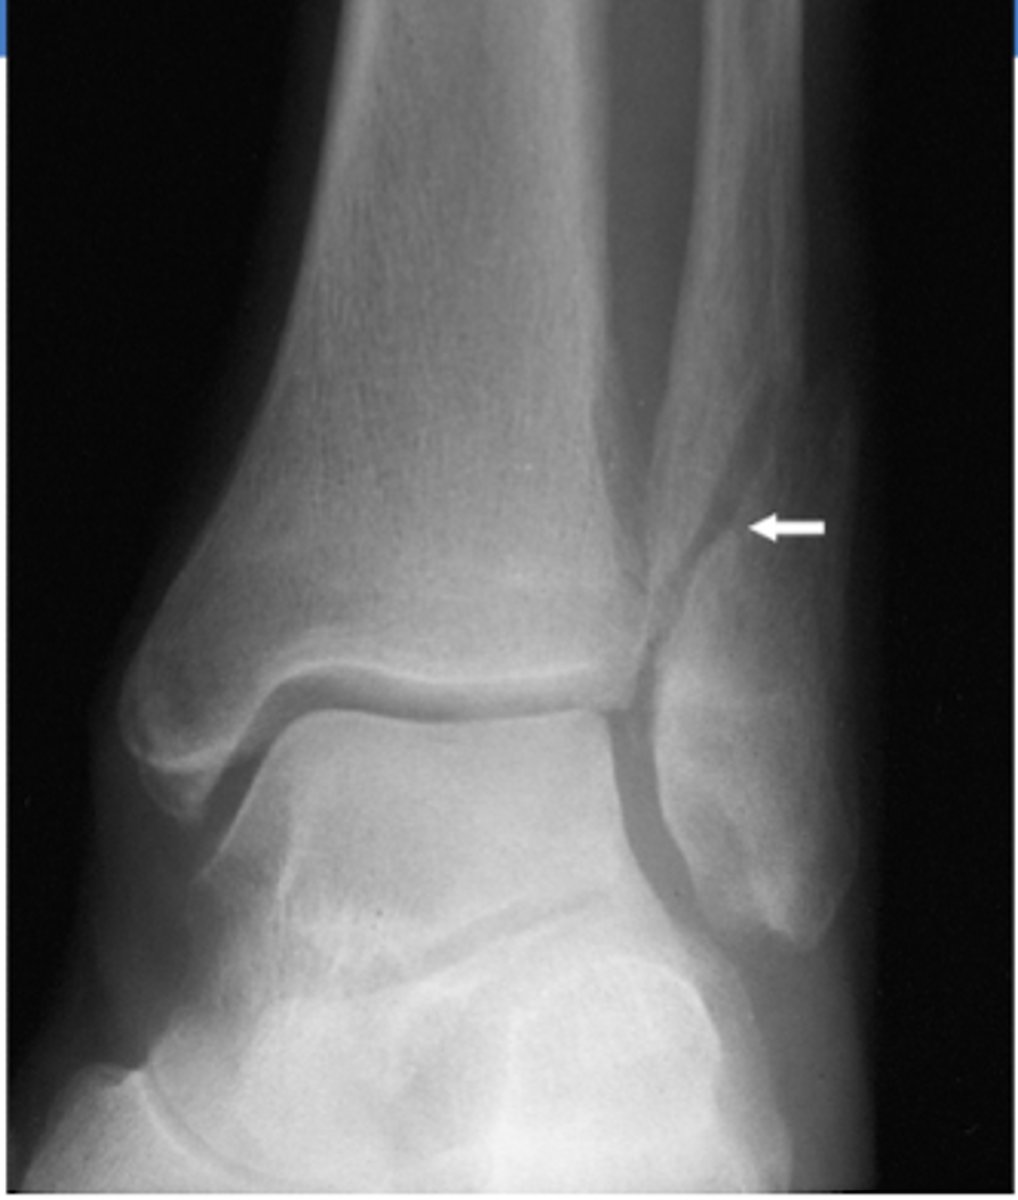

What TWO XR findings are consistent with a Maisonneuve fracture?

Tear of the tibiofibular ligament

Widening of the ankle mortise medially